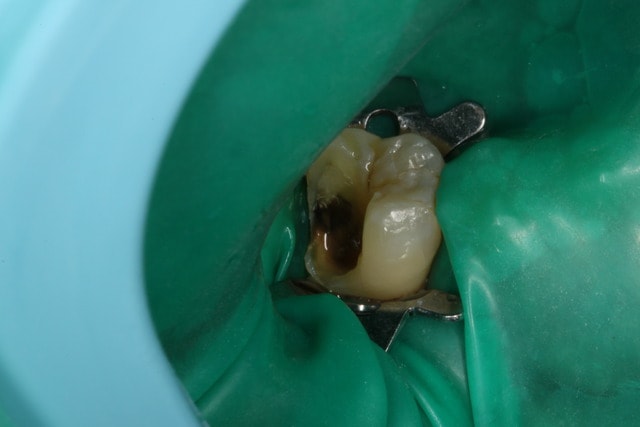

Un petit onlay du dimanche dernier qui m'a fait plaisir. A souligner le travail du prothésiste, content de son boulot après avoir vu les photos.

Dent vitale. Il y avait un compo OD et le pan V a lâcher. Limite supra-gingivale.

Ci joint une autre vue.